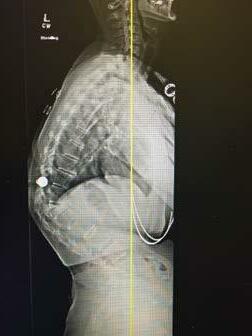

Dr. Yevgeniy Khavkin, the founder of Khavkin Clinic, was raised in Moscow, Russia. He was Inspired to go into the medical field by his mother, a pediatric surgeon, and started his exposure to medicine at age 14 by assisting his mother in surgeries.

Dr. Khavkin started medical school in Moscow when he was 16 and, after his family relocated to the US, transferred to medical school at the University of Chicago, where he also completed his neurosurgical training.

After finishing spine fellowship at Johns Hopkins University, Dr. Khavkin became the director of the neurosurgical spine program at Northwestern University before moving to Las Vegas in 2010. One of only a few fellowship trained spine neurosurgeons in Las Vegas, Dr. Khavkin pioneered a number of spine surgery techniques and was the first surgeon in Nevada to perform complex spine oncological procedures such as sacrectomies and en bloc spondylectomies.

Dr. Khavkin: Khavkin Clinic is a multispecialty practice that includes Las Vegas Neck and Back, Las Vegas Sinus and Las Vegas Headache. We pride ourselves on the comprehensive approach to the diagnosis and treatment of the diseases of the nervous system and the spine.

Even though my expertise is in spine surgery, most of our patients fortunately do not require any surgical treatment and we guide them down the non-surgical path to make sure they get better and return to the pain free life.